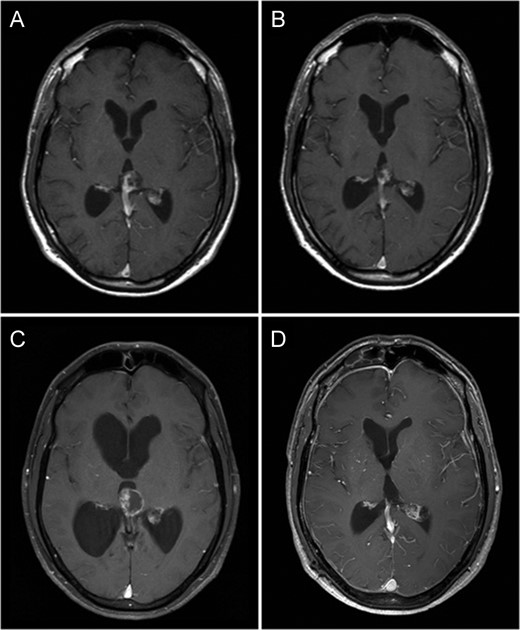

Fat saturated axial gadolinium enhanced T1 weighted MR Brain Image Series (A—July 2000, B—October 2003, C—July 2009 and D—November 2010). Image A demonstrates a heterogeneously enhancing lesion involving the pineal gland with enhancing solid as well as cystic components. Image B demonstrates a reduction in size of this lesion following radiation therapy. Image C demonstrates a prominent increase in the cystic component of the lesion associated with obstructive hydrocephalus. Image D demonstrates no residual tumour or contrast enhancement 1-year following surgery.

The patient received 50 Gy/28 fractions of whole brain radiation therapy, which corresponded with reduction in size of the mass. He made an excellent recovery with complete resolution of his symptoms. He was kept under radiological surveillance for a period of 5 years with no signs of progression (Fig. 1B).

Nine years after his initial presentation, the patient represented with worsening headache, staggering gait and mild memory impairment. Imaging revealed an increase in size of the pineal mass, with a marked enlargement of the cystic component, associated with extension into the third ventricle and obstructive hydrocephalus (Fig. 1 C).

Although histopathological diagnosis of the pineal mass was not established at the very first presentation, we believe on clinicoradiological grounds, that the original pineal mass was an iGCT, and hence this represents a genuine example of iGTS. We hypothesize, using clinicoradiological correlation, the initial diagnosis would favour that of a mixed germ cell tumour with germinomatous as well as teratomatous components. The imaging at presentation revealed a heterogeneously enhancing predominantly solid lesion with some cystic components—this would be inconsistent with a benign mucinous (e.g. enteric) cyst, and hence the enlarging residual mass cannot simply represent an enlarging recurrence of a simple neuro-enteric or related cyst. MR spectroscopy was unavailable for further evaluation of the tumour.